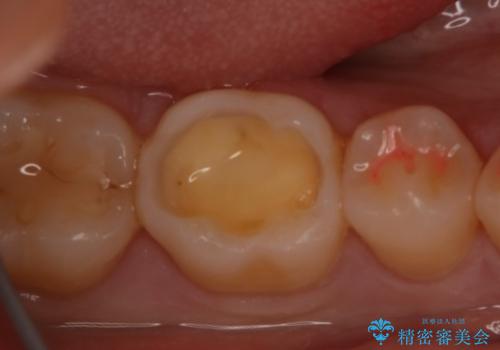

- 右下奥歯の虫歯治療を希望された患者様です。

保険の材料が劣化し、直下で虫歯の存在が確認出来ました。

セラミックを希望されたので形態・切削量を考慮し、セラミックインレーでの治療を計画しました。

虫歯が広く進行していましたが神経には到達していなかったので、予定通りセラミックインレーでの治療を行いました。